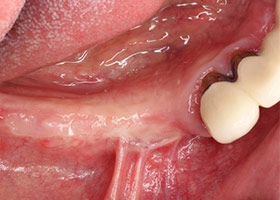

9.完成補骨手術後的健康牙床。

10.植入人工牙根於健康的牙床。